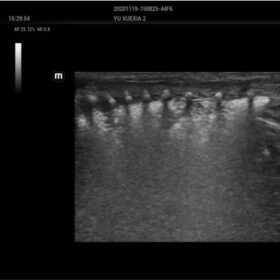

The ZST+ platform is a remarkable advancement, marking a significant evolution in ultrasound technology. It revolutionizes the processing of ultrasound metrics, moving away from the traditional beam-forming approach to channel data-based processing. This breakthrough eliminates the longstanding trade-off challenges between spatial resolution, temporal resolution, and tissue uniformity. The result is outstanding image quality, providing limitless imaging solutions with continuous enhancements.

- Dehaze-improving image contrast resolution with deep presentation